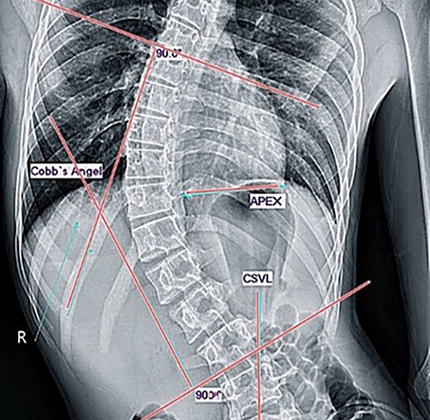

أهم العوامل التي تؤثر على تصحيح دوران الفقرات داخل حزام اعوجاج العمود الفقري مقدمة: لماذا نهتم بدوران الفقرات في اعوجاج العمود الفقري؟ يُعد اعوجاج العمود الفقري عند المراهقين حالة معقدة لا تؤثر فقط على

التنبؤ بنتائج حزام اعوجاج العمود الفقري :الفرق بين الأشعة داخل الحزام وخارجه يُعد اعوجاج العمود الفقري عند المراهقين من أكثر حالات التشوهات الشائعة خلال مرحلة النمو، ويُعرف طبيًا باسم “الجنف مجهول السبب عند المراهقين”.